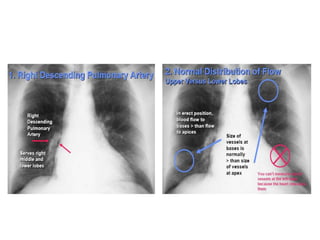

Pulmonary Vessels

1. Measure the right descending Pulmonary artery

Diameter- (16mm in Male & 15mm in Female)

2. Distribution of flow from apex to base

• At first intercostal space– normal vessels not more than 3

mm in diameter

• Erect- Lower lobe vessels prominent

• Supine- Equalize

3. Distribution of flow from central to peripheral -

tapering

• Vascular lung markings- Central 2/3rd

Pulmonary Vessels 1. Measurethe right descending Pulmonary artery Diameter- (16mm in Male & 15mm in Female) 2. Distribution of flow from apex to base • At first intercostal space– normal vessels not more than 3 mm in diameter • Erect- Lower lobe vessels prominent • Supine- Equalize 3. Distribution of flow from central to peripheral - tapering • Vascular lung markings- Central 2/3rd